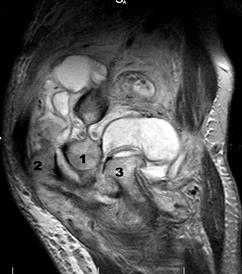

Ревматоидный артрит, III ст. субхондральные эрозии (1) и краевые узуры (2) дистального эпифиза плечевой кости, наличие суставного выпота (3) и массивная гипертрофия синовиальной оболочки (4).

Хронический продуктивно-пролиферативный синовит: гипертрофия синовиальных ворсин и формирование агрессивной грануляционной ткани - паннус. Пролиферация визуализируется в виде участков низкого или среднеинтенсивного МРС по Т2 и Т1, покрывающих поверхность заворотов, жировых ямок и капсулы сустава (от мелких неровных узелков до гомогенных слоистых отложений).

1. Плечевая кость, 2. локтевая кость, 3. лучевая кость